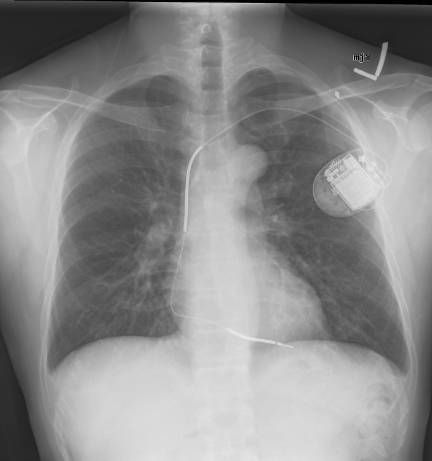

An automated implantable cardioverter defibrillator (AICD)

"The ICD is the first-line treatment and prophylactic therapy for patients at risk for sudden cardiac death due to ventricular fibrillation and ventricular tachycardia."

So no going through metal detectors at an airport. Let's see if this one comes with an app.